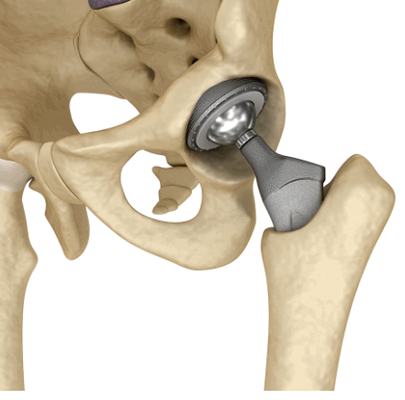

Эндопротезы коленного сустава

После эндопротезирования могут появиться патологические симптомы. Это - показание к проведению МРТ для уточнения осложнений. Когда врач назначает подобную процедуру, некоторые пациенты боятся нагревания или смещения искусственного сустава. Можно ли делать МРТ с эндопротезом, зависит от особенностей конструкции. Описание изделия имеется в паспорте протеза. Информацию можно уточнить в клинике, где проводили операцию.

Вариант протеза тазобедренного сустава